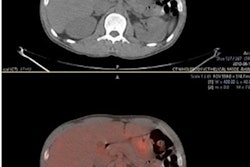

Coronal short tau inversion-recovery (STIR) (A), FDG-PET (B), and FDG-PET/MRI (C) fused images show how the hybrid modality detected right supraclavicular fossa and right paratracheal lymphadenopathy, as well as a right lung nodule (arrows), in a 14-year-old male with Hodgkin lymphoma. Images courtesy of the Journal of Nuclear Medicine.As for response assessment, FDG-PET/CT spotted six true positives (0.9%), which would indicate an incomplete treatment outcome, among a total of 609 disease sites. By comparison, FDG-PET/MRI detected five of those six true positives (0.8%), with one incomplete treatment response missed due to a "perceptual error." When the researchers corrected for that miscue, they achieved "perfect agreement" for staging and "excellent response assessment agreement" between FDG-PET/MRI and FDG-PET/CT, they added. Again, there was no statistically significant difference.